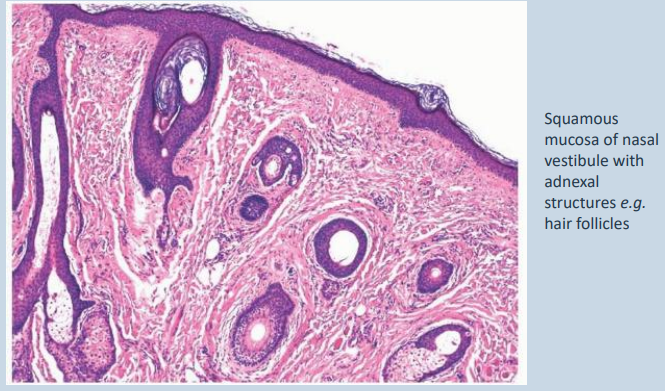

Cutaneous region (nasal vestibule)

• Rostral region – keratinised stratified squamous epithelium

• Mid vestibule – thinner, non-keratinsed stratified squamous epithelium

• Caudal region – transitional zone (approaching respiratory epithelium) – varies from stratified cuboidal to non-ciliated pseudostratified columnar